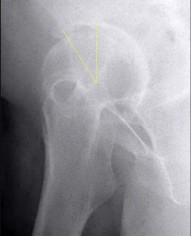

A 12-year-old male with a BMI > 95th percentile presents with hip pain and is diagnosed with a Slipped Capital Femoral Epiphysis (SCFE). Which of the following is the strongest indication for prophylactic in situ pinning of the asymptomatic contralateral hip?

Correct Answer: Underlying endocrinopathy, such as hypothyroidism

Explanation:

Prophylactic pinning of the contralateral hip in SCFE is controversial but is strongly indicated in patients with underlying endocrinopathies (e.g., hypothyroidism, growth hormone deficiency) or renal osteodystrophy. These conditions dramatically increase the risk of bilateral involvement. Other indications include inability to follow up, radiation therapy, and open triradiate cartilage (though age and triradiate status are debated, endocrinopathy is universally agreed upon).

A 13-year-old overweight male presents with an acute exacerbation of chronic right groin and knee pain. He walks with an externally rotated gait. Radiographs confirm a severe Slipped Capital Femoral Epiphysis (SCFE). Pathophysiologically, the slippage in SCFE occurs primarily through which specific histological zone of the proximal femoral physis?

Correct Answer: Zone of hypertrophy

Slipped Capital Femoral Epiphysis (SCFE) typically occurs due to mechanical shear forces across a weakened physis during the adolescent growth spurt. Histologically and biomechanically, the weakest layer of the growth plate is the zone of hypertrophy. The slippage classically occurs through this layer because the chondrocytes are enlarged, and the extracellular matrix is sparse compared to the reserve or proliferative zones, making it highly susceptible to shear stress.